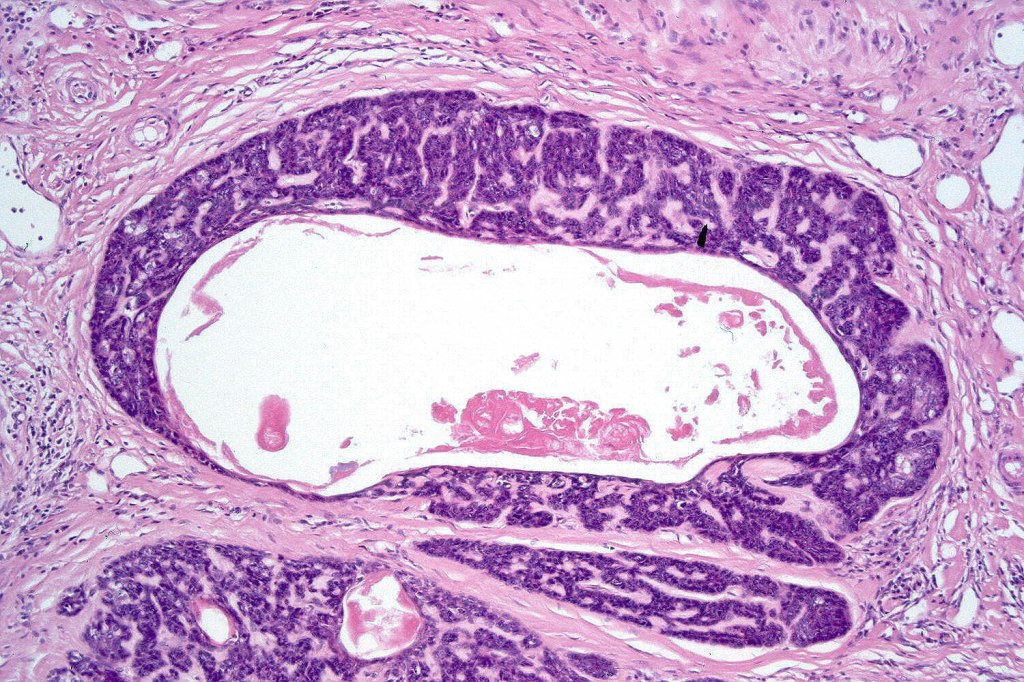

Histological features

•Variable continuity with epidermis

•Multinodular with surrounding collagenous stroma

•Random distribution of basaloid cells & sebocytes (<50% sebocytes)

•Duct formation, often with holocrine secretion generally present

•Mitoses sparse to conspicuous

•Absent peripheral palisading & retraction artifact

•Cystic variant